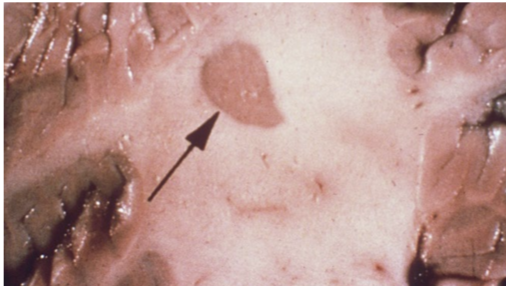

What is this and what disease is it seen in

Plaque in multiple Sclerosis